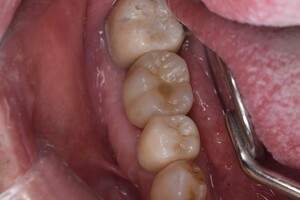

口腔内写真

- Befor

- After

| 年齢 | 50代・男性 |

| 主訴 | 左上7番 左下5番7番 |

| 治療内容 | ・インプラント埋入 ※1:GBR(骨造成)・・・骨再生誘導法。骨の高さや厚みを人工骨や人工膜などを使用し再生する方法 |

| 治療費 | 合計:1,809,500円(税込) ■内訳 ・左上7番 ・左下5番7番 |

| 治療期間 | 左上7番約1年 左下5番7番約10ヵ月 |

| 治療方針 | 左上7番は昔他院で被せものをしており、被せものの中が歯ぐきの中まで虫歯になっていたため抜歯せざるを得ない状態だった。抜歯と同時に骨造成を行い、骨が出来るまで4ヵ月待ってからインプラントを埋入した。 ※2ポンティック・・・歯のない部分を補うダミーの歯。 |

| 担当者所見 | 元々金属の被せものが多く入っていたため、2次カリエス※3が多かった。今回は金属ではなく、ジルコニアを使用し、2次カリエスにならないよう、患者様にはブラッシング指導とメンテナンスの重要性をお伝えした。 ※3二次カリエス・・・詰め物や被せものを入れた歯が虫歯になること。 |